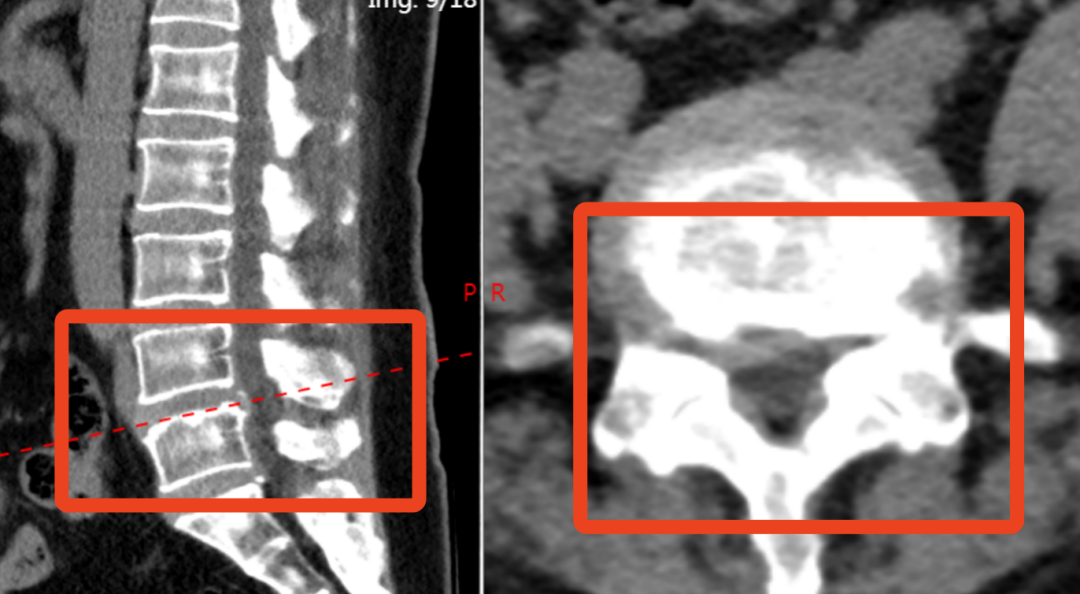

62 岁的钟阿姨(化姓)因反复腰痛 10 余年加重伴右下肢疼痛麻木 2 月入院,她被诊断为腰椎间盘突出症、腰椎椎管狭窄症。

科室为其实施椎间孔入路腰椎融合术,术后症状较前缓解,佩戴护具即可下地活动。

该技术通过减压、植骨融合与内固定,为不稳定的脊柱提供支撑,改善患者长期腰痛问题。